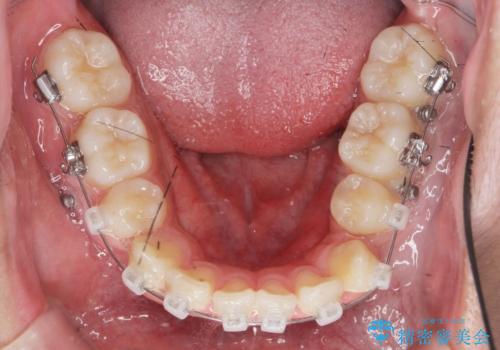

- ワイヤー矯正

噛み締めが強く、治療に時間がかかりましたが矯正治療の仕上がりに満足いただくことができました。